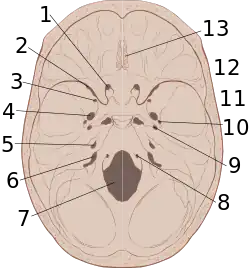

The interior of the skull has sharp ridges by which a moving brain can be injured.